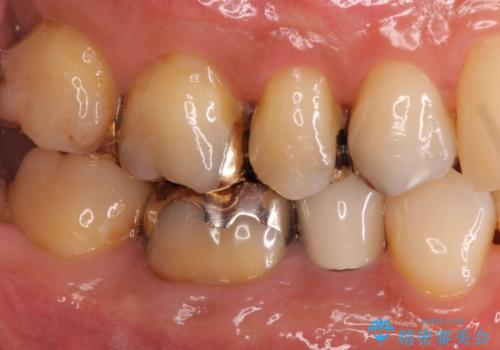

- 銀歯をすべてやり替えたいとのことで来院された患者様です。

再根管治療が必要なところは再根管治療から、そうでないところは補綴物のみをやり替えていくこととなりました。

銀歯のやり替えと並行してホワイトニングも行いました。

結果的には銀歯がすべて白くなり、前歯のガタつきもある程度改善され大変喜んでいただけました。